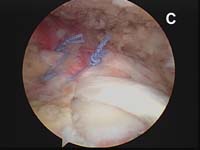

For the most common type of rotator cuff tears, the tendon of the rotator cuff muscle called the supraspinatus will have torn and pulled back slightly from its normal attachment at the greater tuberosity atop the humerus. These smaller tears which are "non-retracted" or "minimally-retracted" only need to be freshened or débrided back to stable, healthy tendon tissue, then mobilized back to the tuberosity and fixed in place. (See Fig. 9) When using an all arthroscopic technique, the surgeon will employ special devices called "suture anchors" to hold the tear in position when it heals. These "anchors" can be made of metal or absorbable compounds. They are screwed or pressed into the bone of the attachment site and the attached sutures are used to tie the edge of the rotator cuff in place.

As tears become larger, they deform and the tendon tissue "shrinks". Thus, larger tears need to be refashioned, repaired side-to-side, or "zipped" closed using a technique called margin convergence. This technique is analogous to zippering shut an open tent flap. The rotator cuff tissue is freed from a scarred, retracted position and repaired side-to-side to ‘close the tent flap’ and restore the tissue over the top of the humeral head. (See Fig.4 and Fig.10) The repaired cuff tissue is then fixed to the site it originally tore away from using specially-designed implants called suture anchors. These are metallic or absorbable plastic devices that secure sutures to the bony attachment. The sutures are then sewn through the torn edge of the cuff to complete the repair.